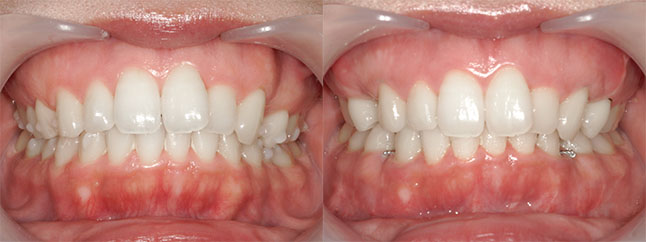

【治療内容】出っ歯、口元の膨らみが気になると当院を受診されました。上の前歯と歯茎が前方にポジショニングしており、下の前歯も歯茎から前に出ておりました。

<上下セットバック>

歯と歯茎を上は、5oバック、2oアップ、下は5oバックし固定しました。

※口ゴボ感が改善し、ご満足いただけました。

※afterは術後3か月時の写真です。

【費用】上下セットバック 2,307,800円(税込)

【リスク】感染・腫れ・出血・知覚鈍麻など